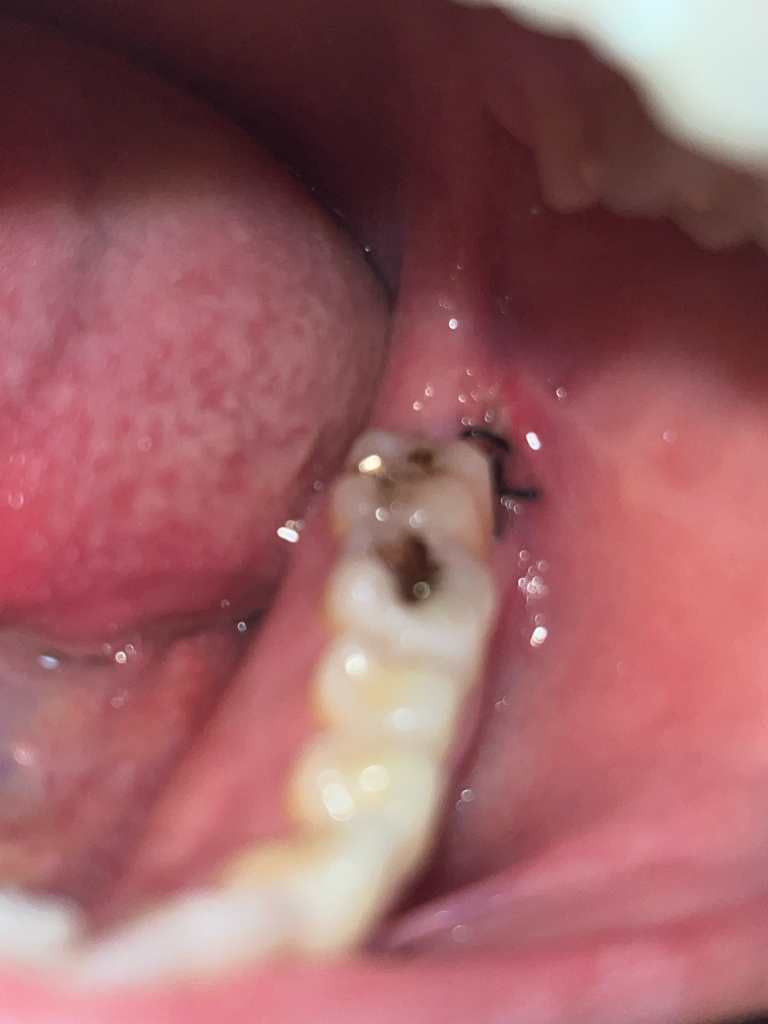

매복사랑니 발치 후 5일이 지났는데 통증이 아직 심해요. 드라이소켓인가요?

19일 오전 10시경에 왼쪽 아래 완전매복사랑니 발치를 했습니다. 발치 후 주의사항 전부 지켰고 처방해주신 약도 전부 다 복용한 상태입니다.

발치 후 5일 가량 지났는데 아직 밥 먹기도 힘들고 자려고 누우면 통증이 심해집니다.. 사진상 잘 안 보이지만 드라이소켓일 가능성이 있나요? 통증은 언제부터 완화될까요..?

• 2번 째 사진